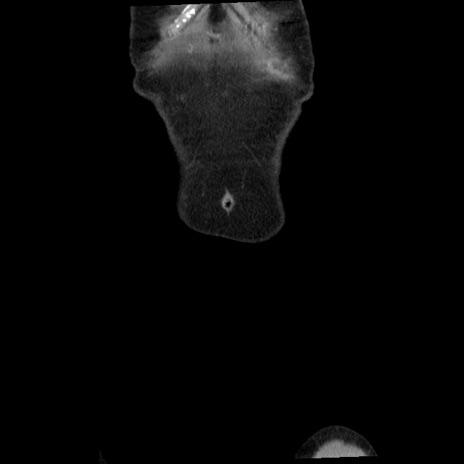

矢状断像